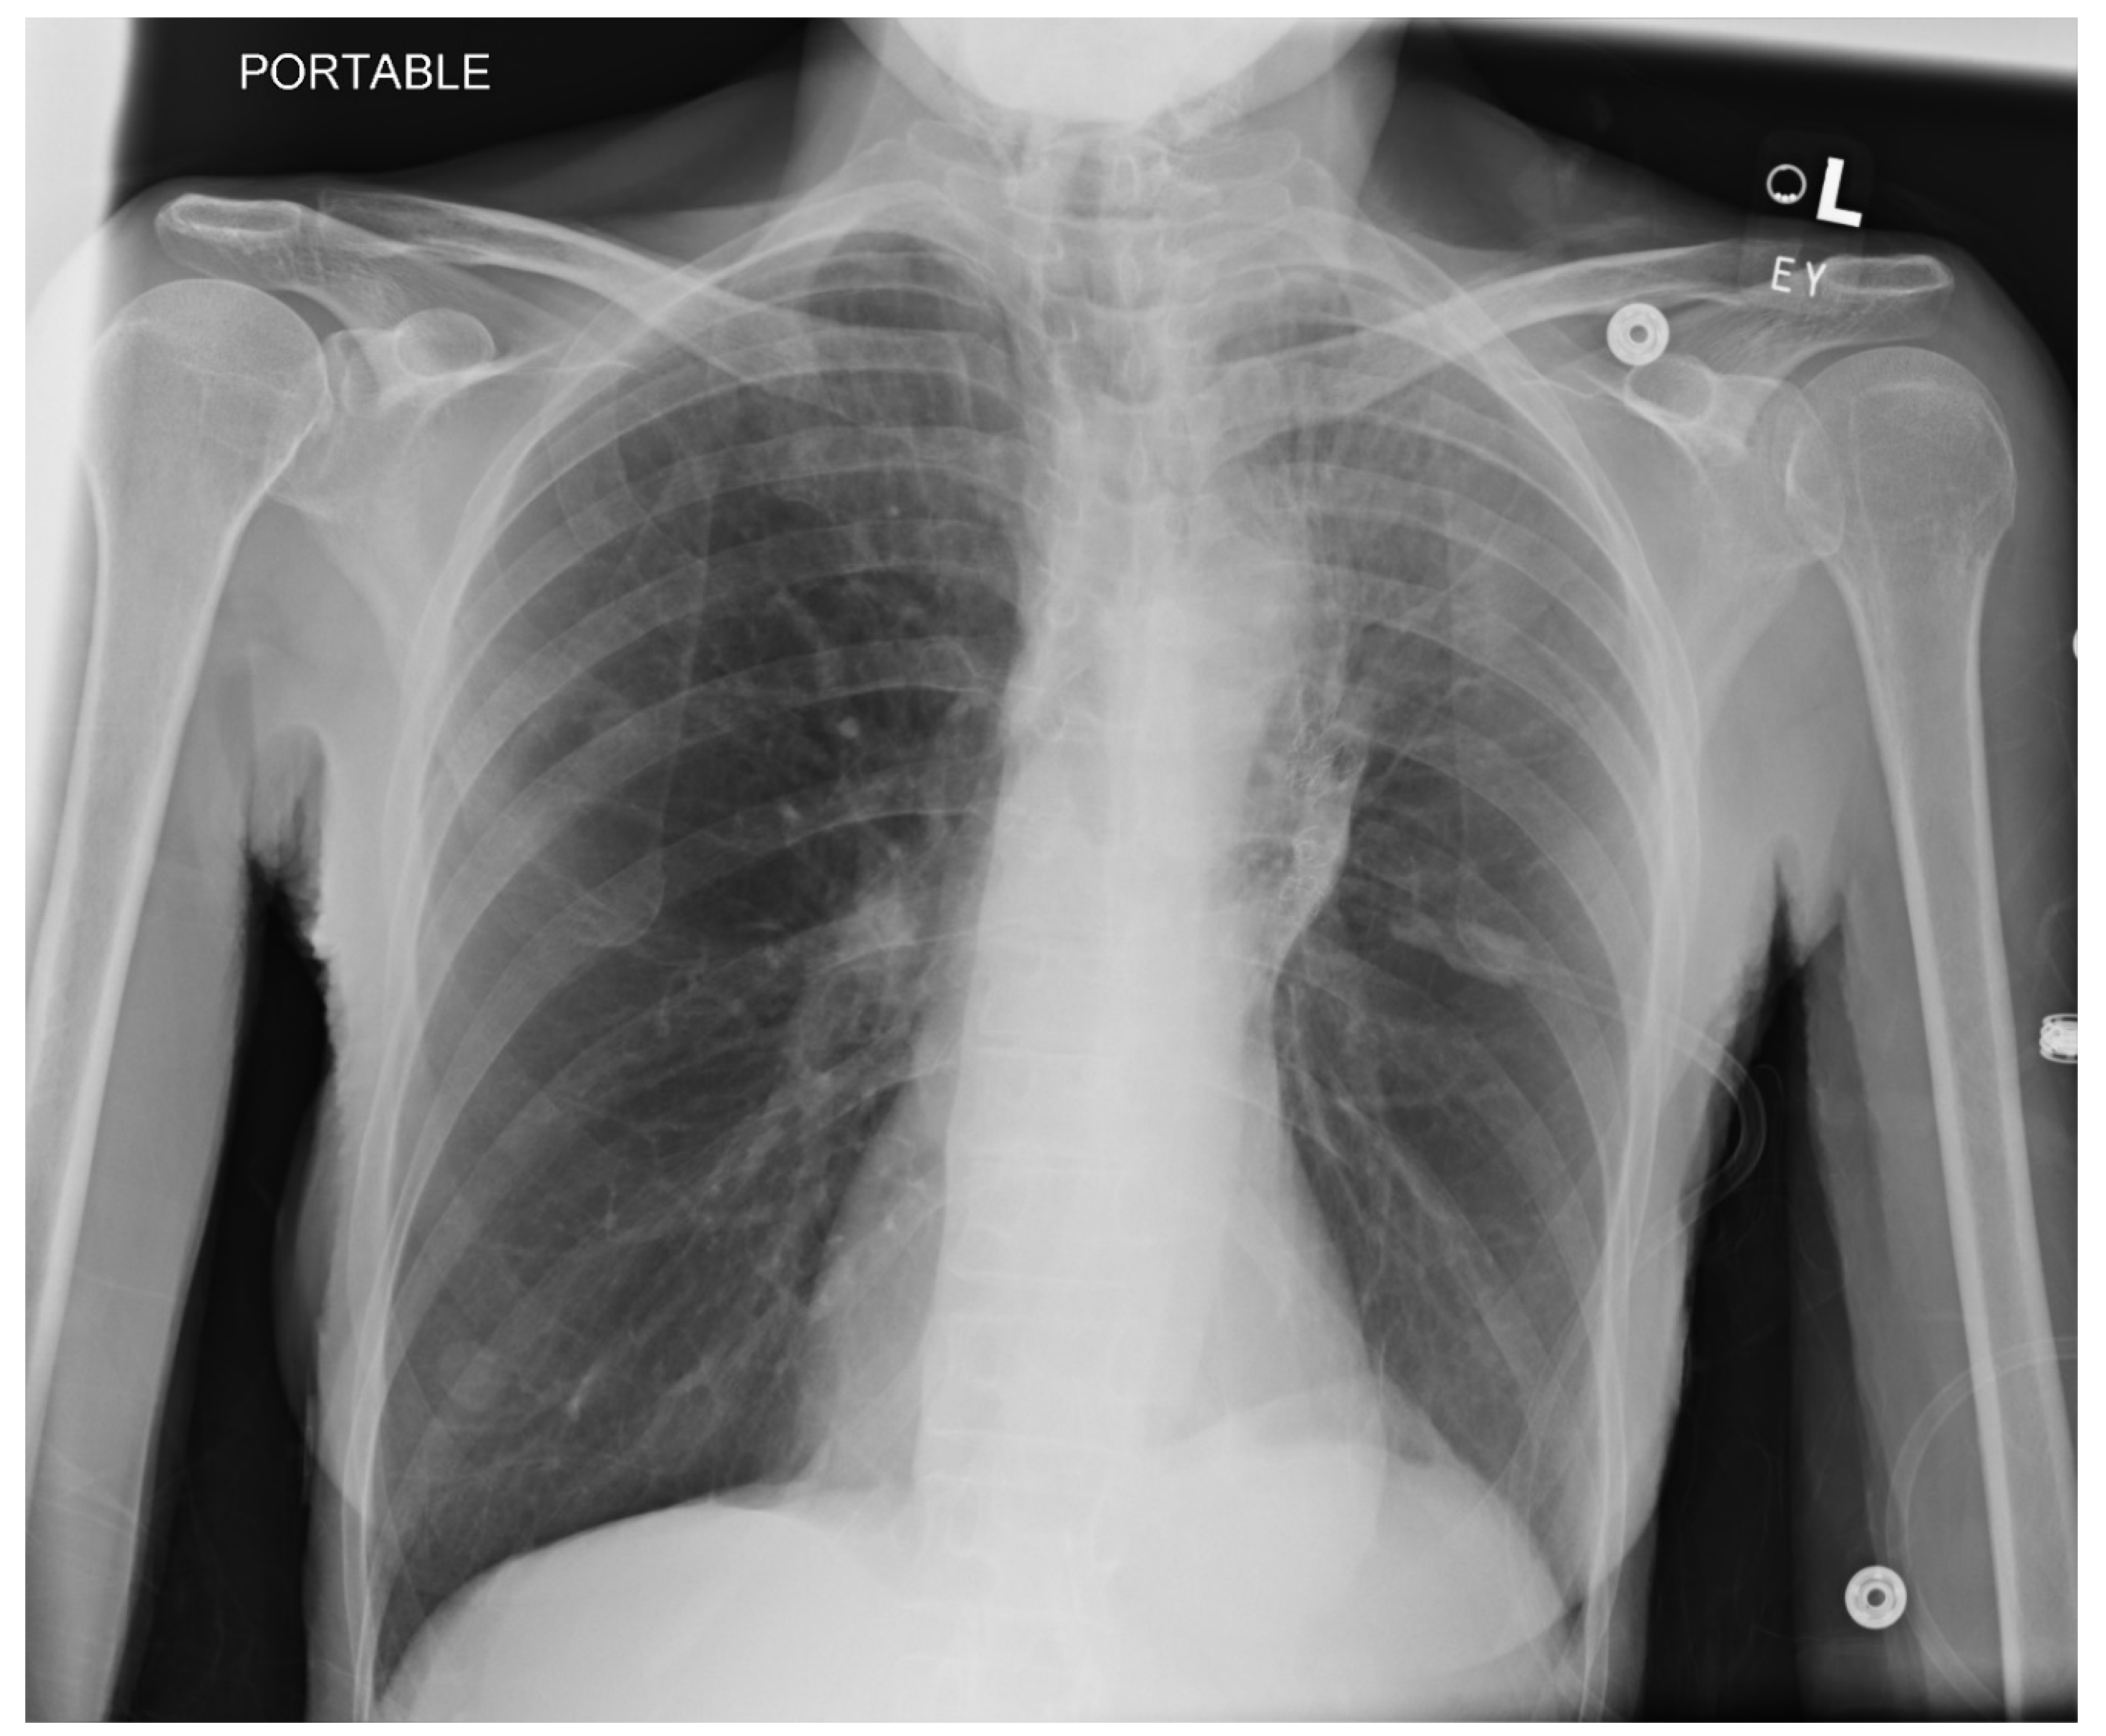

Pneumothorax (Figure 1, Figure 2, Figure 3 and Figure 4) developing after the placement of endobronchial valve (Figure 5) is usually managed by pulmonologists; however, anesthesia providers should be aware. Dijk et al. published their revised expert statement that addresses the issue of pneumothorax extensively [53]. The development of pneumothorax is related to compensatory expansion of the untreated ipsilateral lobe. Such an expansion might result in the rupture of blebs, bullae, and fragile lung tissue [54]. The bronchopleural fistula that develops leads to air leak, which can get worse and become clinically significant very quickly. Pneumothorax can also develop in the vacuum created by therapeutic lung collapse (pneumothorax ex vacuo). The air enters the potential space from the ambient tissues and blood [55]. As there is no bronchoalveolar fistula in this situation, a chest drain is not necessary, and the pneumothorax will spontaneously resolve over time.

Pneumothorax can develop in the immediate postoperative period, in the post anesthesia care unit or within the first 3 days [46,56]. Valipou et al. published their management algorithm for pneumothorax [57]. Nearly 80% of them happen in the first 48 h, 10% in about 3-5 days, and 10% after day 6 [58,59]. Both anesthesia providers and bronchoscopists should be particularly vigilant about the development of tension pneumothorax. Certain post procedural protocols- (cough suppression, strict bed rest, not letting to elevate the arm above shoulders) are employed at Jefferson to minimize the pneumothorax risk. Most pneumothoraces ‘s are treated conservatively with serial imaging. some may require chest tubes and rarely valve removal.

Figure 3. CXR Interval placement of a left chest tube. Likely residual loculated pneumothorax at the left lung base. Left upper lobe opacification.

Figure 4. CXR Left upper lobe volume loss (day 2). Moderate left pleural effusion compatible with hemothorax (which was seen on CTscan). Stable cardiac silhouette. Left apical chest tube. Left hilar endobronchial valves.